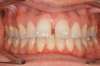

Vues avant le traitement